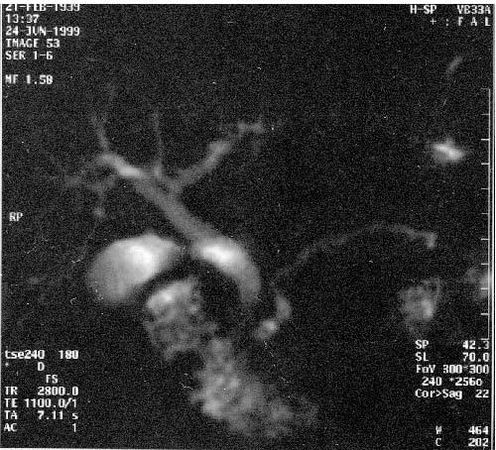

В последние годы появился новый неинвазивный метод – магнитно-резонансная холангиопанкреатография который позволяет визуализировать желчные и панкреатические протоки без инвазивных вмешательств и введения контрастных веществ. Это исследование осуществимо у всех больных, не дает осложнений и позволяет получить такую же информацию, как и при одновременном применении КТ, ангиографии (АГ) и эндоскопическая ретроградная холангиопанкеатография (ЭРХПГ) (рис. 101. а, б).

Рис. 101. Магнитнорезонансная холангиопанкреатикография. Рак головки ПЖ. А – отмечается дефект наполнения (2) в панкреатической части холедоха (1) на протяжении 1 см. Опухоль диаметром 1,5 см была выявлена только интраоперационно. Б – отмечается дефект (3) в месте слияния общего желчного (1) и панкреатического (2) протоков. Имеется супрастенотическое расширение протоков. Опухоль диаметром 3 см была выявлена при УЗИ, КТ и интраоперационно